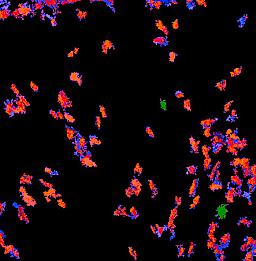

Pancreatic ductal adenocarcinoma is a lethal disease with limited treatment options and poor survival. We studied 83 spatial samples from 31 patients (11 treatment-naïve and 20 treated) using single-cell/nucleus RNA sequencing, bulk-proteogenomics, spatial transcriptomics and cellular imaging. Subpopulations of tumor cells exhibited signatures of proliferation, KRAS signaling, cell stress and epithelial-to-mesenchymal transition. Mapping mutations and copy number events distinguished tumor populations from normal and transitional cells, including acinar-to-ductal metaplasia and pancreatic intraepithelial neoplasia. Pathology-assisted deconvolution of spatial transcriptomic data identified tumor and transitional subpopulations with distinct histological features. We showed coordinated expression of TIGIT in exhausted and regulatory T cells and Nectin in tumor cells. Chemo-resistant samples contain a threefold enrichment of inflammatory cancer-associated fibroblasts that upregulate metallothioneins. Our study reveals a deeper understanding of the intricate substructure of pancreatic ductal adenocarcinoma tumors that could help improve therapy for patients with this disease.